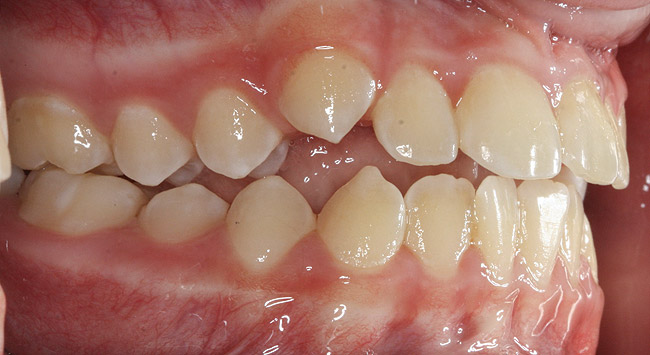

The point of obstruction tends to determine the type of skeletal impact. Nasal obstruction from enlarged turbinates, blocked ostium maxillare, deviated septum, or nasal valve stenosis creates Angle occlusions of Class I, II, and III equally (Figure 8). The maxilla in these cases is positioned posteriorly and the mandible is posterior-inferior. The facial type is most commonly dolicocephalic. Blockage of the airway predominately by the adenoids will create growth patterns that yield mostly Class II occlusions and anterior open bite with both jaws located posterior-inferiorly. Facial type is again dolicocephalic with the typical long-thin “adenoidal” face49 (Figure 9 through Figure 12). If the tonsillar tissue is responsible for the airway obstruction, the tongue will have an abnormal resting posture. Class III occlusions will be more common with the maxilla normal or posterior placed (Figure 13 through 15). The tongue may direct the mandible anteriorly or, because the tongue is not in the roof of the mouth driving A point anterior, the maxilla will become bimaxillary retrusive.50 In some cases, the anterior posture of the tongue will create an open bite. This is incorrectly referred to as a tongue thrust. The impact from a thrust does not alter the tooth position. Long-term, low forces cause tooth movement. The posture of the tongue against or between the anterior teeth due to the excessive tonsillar size creates the open bite (Figure 16 and Figure 17). Facial types in this group are more brachyfacial. Lastly, if the airway is blocked through a combination of factors, the Angle classification will be either Class II or III. The maxilla will be in a normal location and the mandible will be the affected arch (Figure 18). These craniofacial changes are not restricted to OSA; all SDB will create unique alterations depending on the patient compensation. Children with UARS have been reported to display high, narrow palates, dolicofacial form, and a Class II malocclusion, indicative of largely adenoidal blockage.51

(21.) Six-year-old male presents nocturnal bruxism, habitual snoring, and behavioral issues. PSG reports an AHI of 9.6/hr and respiratory effort–related arousal (RERA) of 14.2/hr (Case provided by Kathy French, DDS).

Figure 21